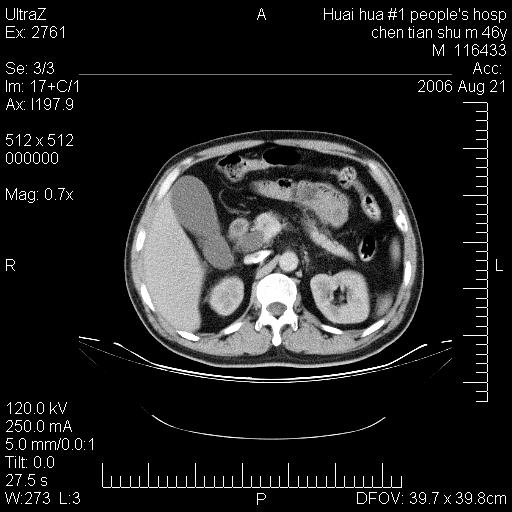

患者,男,46y。腹痛2月,消瘦。

手术病理结果:原发性小肠恶性淋巴瘤(primary gastrointestinal lymphoma,pgil)是原发于胃肠的淋巴网织系统的恶性肿瘤,在结外淋巴瘤中居第一位,该病少见,临床无特异性,诊断困难,术前主要依靠影像学诊断。胃肠道本身具有较丰富的淋巴组织,因而胃肠原发性淋巴瘤是结外淋巴瘤最常见的部位,文献报道约占胃肠道恶性肿瘤的1%~4%,其中胃约占50%~70%,小肠约占35%~70%,结肠约占4%~6%。影像检查在pgil的诊断及分期中有重要的作用,ct是很有价值的检查方法。

胃肠淋巴瘤病理特点:胃肠道原发性淋巴瘤起源于胃肠壁固有层和黏膜下层的淋巴组织即胃肠粘膜相关淋巴组织(malt),多为粘膜相关淋巴瘤。病理上通常为非霍奇金淋巴瘤,且决大多数来源于b淋巴细胞,很少见于霍奇金淋巴瘤。胃肠原发淋巴瘤比胃肠道癌的发病率要低的多,最常见于胃,其病因可能跟幽门螺杆菌感染有关。幽门螺杆菌能引起胃粘膜损害,引起炎性及免疫反应,淋巴细胞聚集并形成滤泡,可影响胃的正常生理功能,导致胃淋巴瘤的发生。单纯性小肠淋巴瘤是常见好发于回盲末端,受累的肠段较长,可单发、多发,甚至累及整个小肠。原发性大肠淋巴瘤罕见,以直肠和盲肠最多见。病变大体观可表现为胃肠腔内外的肿块,也可表现为从黏膜下到浆膜面肠壁的纵向浸润,并且常常伴有肠系膜淋巴结肿大。任何情况下,肿瘤几乎总是导致一定程度的肠壁增厚,可对称或不对称,病变与正常组织间常无明确分界,肠腔可狭窄、正常或动脉瘤样扩张,后者主要是肿瘤在肠壁内浸润,破坏肠壁内植物神经丛所致。以上改变成为ct检测病变的病理基础。

肠道淋巴瘤的ct表现分为4类

1) 壁内浸润型, (2)多发结节型, (3)肠系膜受累伴腔外肿块型(本型就是),(4)肿块型。